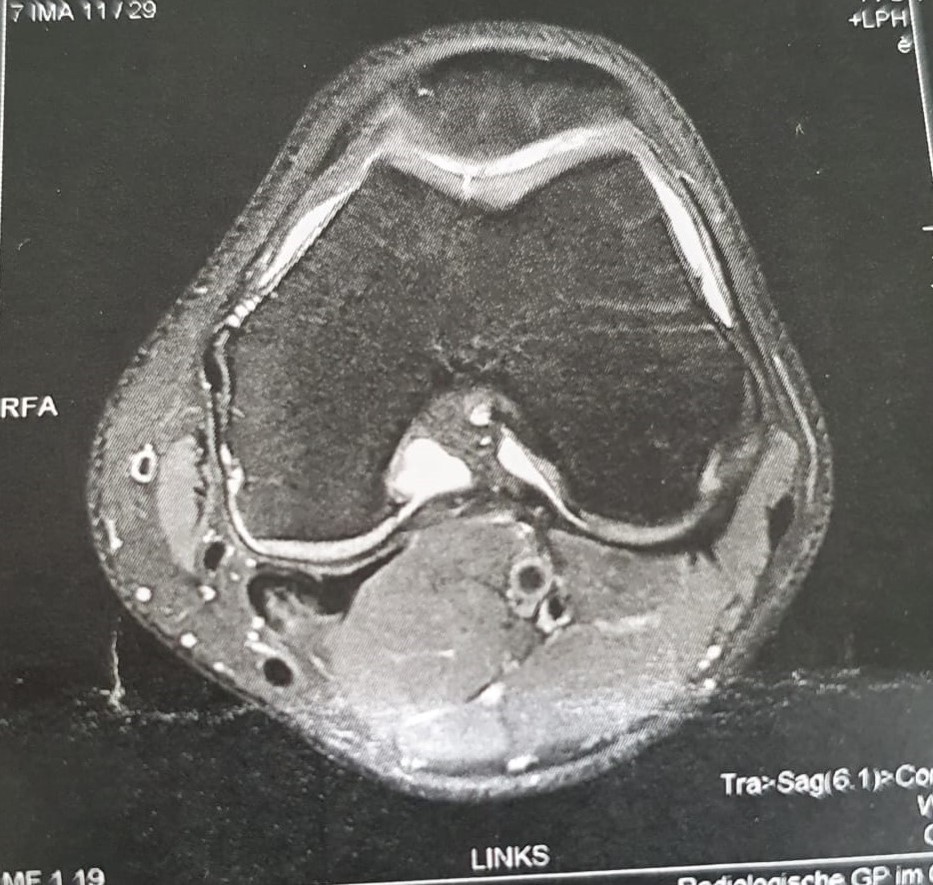

Ich hatte auf einmal Schmerzen im Knie nach einem Urlaub in Sardinien und dieser wurde in den anschliessenden Wochen nach Belastungen wie Fussballtraining und Fitnessuebungen immer groesser, sodass ich mich auf dem Weg zu meinem Sportarzt gemacht habe. Dieser hat mich sofort zum Radiologen/ MRT geschickt. Die darauffolgenden Bilder waren eindeutig. Ein kleiner Riss im Knorpel unter der Kniescheibe, welcher bis auf den Knochen durchgerissen ist (Knorpelschaden 4. Grades; Bilder folgen). Der ehemalige Mannschaftsarzt eines Fussball Bundesligisten verwies sofort auf die Mikrofrakturierung (MF), welche vor allem bei kleinen Knorpelschaeden 4. Grades bei jungen Menschen mit noch gesunden darum liegendem Knorpelgeweben angewendet wird. Eine Zweitmeinung beim naechsten noch aktiven Bundesliga-Mannschafsarzt bestätigte diese Behandlungsmethode und mir wurde langsam klar, dass es jetzt ernst wird.

MRT Bild (Knorpelriss unter der Patella)